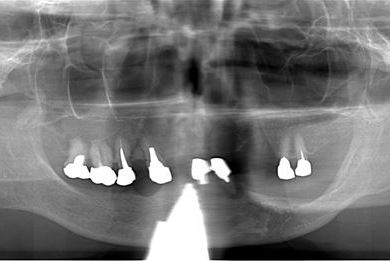

インプラント治療+オーバーデンチャー

| 性別/年齢 | 女性 / 85歳 | ||||||||||||||||||||||||||||||||

| 主訴 | 義歯の調子が悪い。 | ||||||||||||||||||||||||||||||||

| 治療方針 | 下顎に2本インプラントを埋入し、アタッチメントをつけて、オーバーデンチャーを装着し、はずれにくく、安定した義歯を装着する。 | ||||||||||||||||||||||||||||||||

| 治療内容 | インプラント2本(テンポラリーインプラント)、アタッチメント、コバルトクロム床オーバーデンチャー | ||||||||||||||||||||||||||||||||

| 総治療費 | 1,540,350円 | ||||||||||||||||||||||||||||||||

| 治療期間 | 5ヶ月 |